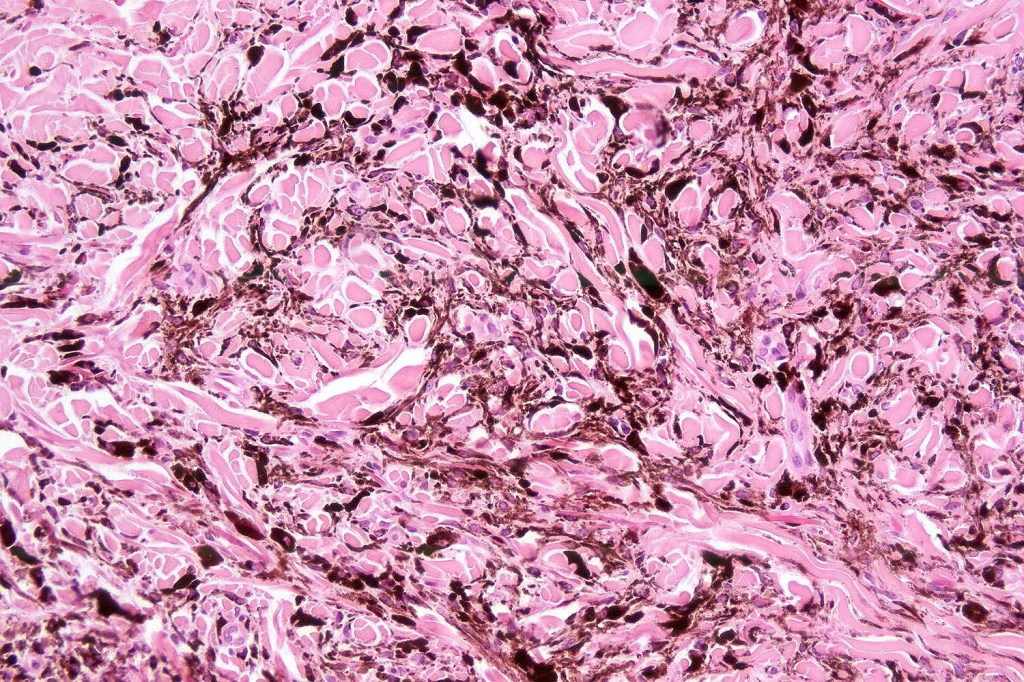

Histologically, it is characterized by a dense population of spindled, dendritic melnanocytes & melanophages with variable fibrosis. It may sometimes represent a component of a combined nevus. Mitotic activity is not usually present and pleomorphism is absent (see atypical blue nevus below). Involvement of the arrector pili muscle is not uncommon.

Very exceptionally, blue nevus also involves the epidermis (compound blue nevus).